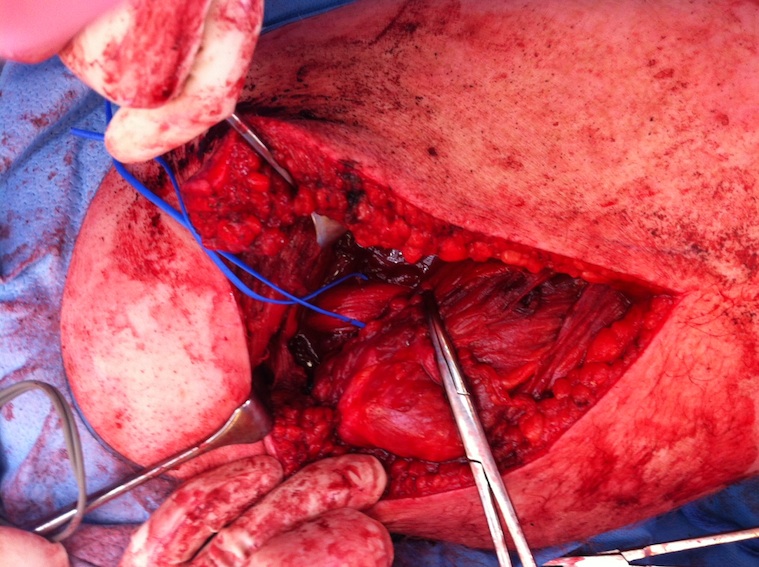

Deep dissection

- identify and preserve sciatic nerve (lateral to hamstring)

Hamstring (*) with sciatic nerve lateral to hamstring (blue vessiloop)